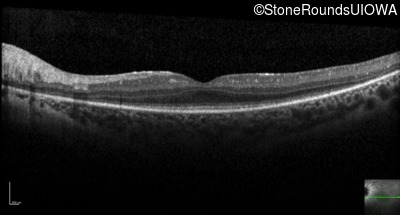

Optical Coherence Tomography - Right - 20/40 -1

Exemplar / OCT Stack